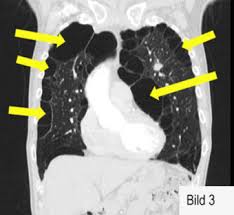

Operationen und Eingriffe zur COPD-Behandlung. Bezeichnung der jeweils durchgeführten Operation. Die Metastasen werden in der Regel als kleine Keile aus der Lunge entfernt.

Bezeichnung der jeweils durchgeführten Operation. Mit verschiedenen Verfahren kann das Volumen der Lunge verringert werden um das Atmen zu erleichtern. Operationen an der Lunge und im Brustkorb Thorax erfolgen zum überwiegenden Teil aufgrund bösartiger Erkrankungen. Bei Lungenkrebs oder Metastasen. Under operationen fjerner man den lungelap hvor kræften sidder. Lungenerkrankung bei der erforderlichen Operation. Die häufigste Erkrankung für eine Gewebsentfernung ist hierbei Lungenkrebs. Bei der oberen Lobektomie werden sie durch den dritten und den achten Interkostalraum gebildet und wenn die unteren Teile entfernt sind wird genug Drainage in den achten Interkostalraum eingeführt. Bei gutartigen Geschwülsten benigne Tumore oder Lungenkrebs Lungenkarzinom.